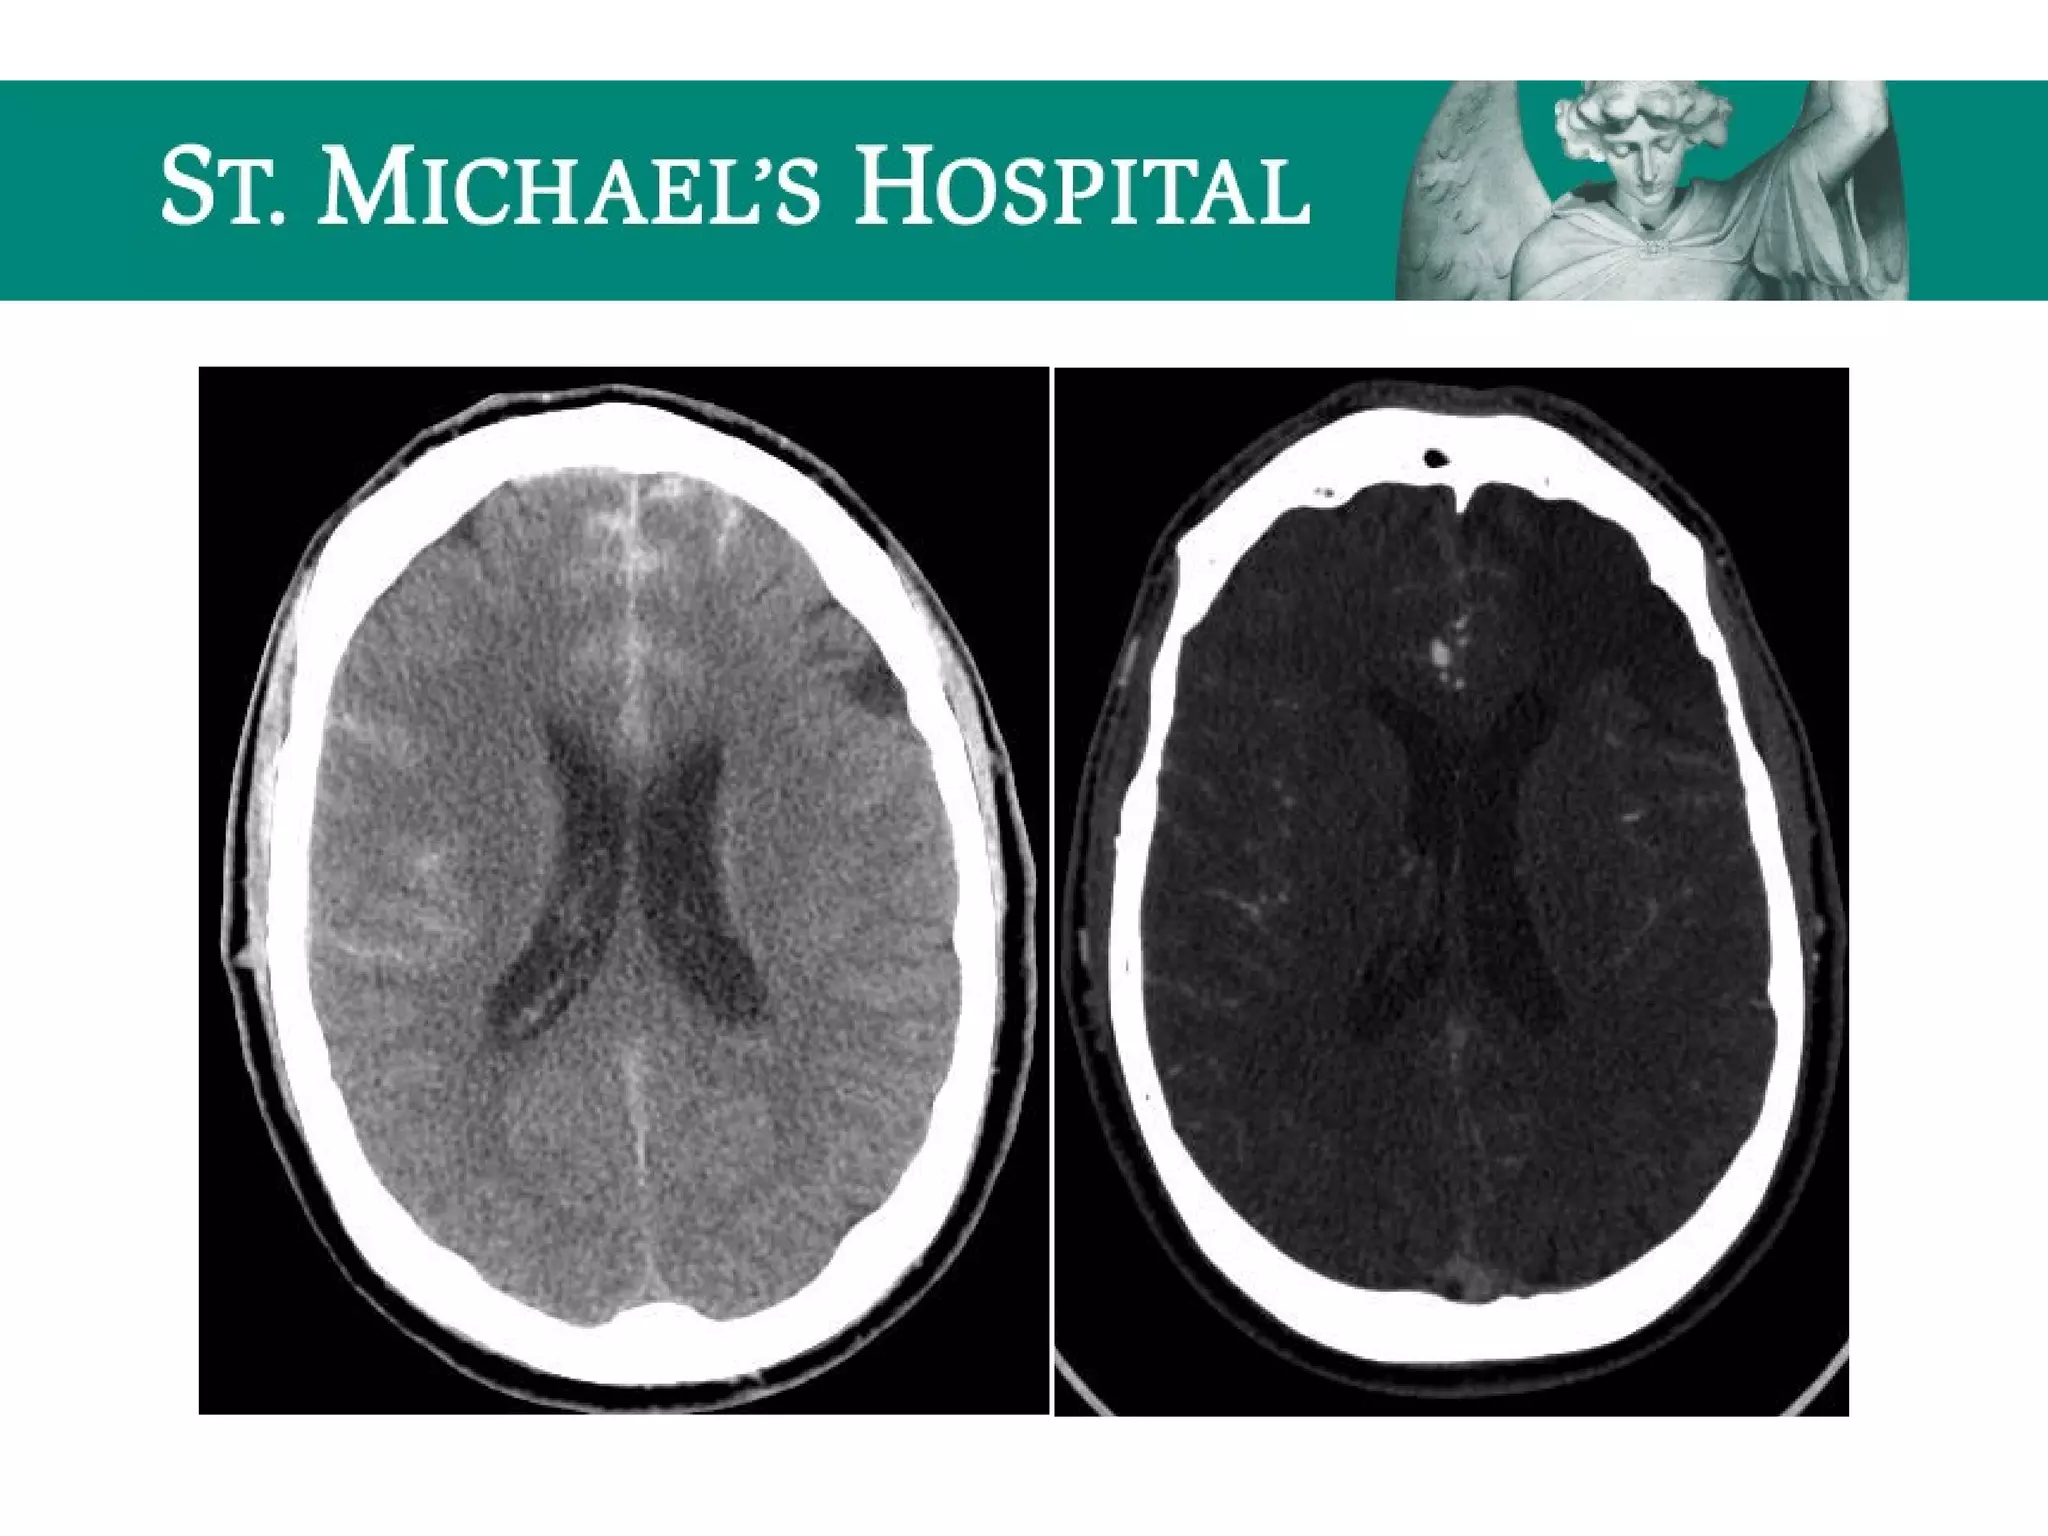

Global Cerebral Ischemia/Anoxic Brain

Injury

 Diffuse brain swelling/edema can result in:

 global loss of gray-white differentiation

 global sulcal/cisternal effacement

 pseudo-subarachnoid hemorrhage

 dense cerebellum

Acute Ischemic Stroke

 Unenhanced CT has low sensitivity – primarily done to rule out

hemorrhage/other causes of patient’s symptoms

 Hyperdense MCA = acute intraluminal thrombus (corresponding loss of

contrast opacification on CTA); seen in 25-50% of acute MCA occlusions.

 Loss of gray-white differentiation:

 insular ribbon sign

 basal ganglia sign

 Sulcal effacement (secondary to cytotoxic edema)